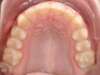

Cas 3 : Description

Encombrement aux deux arcades.Traitement par gouttières.

Avant

Après